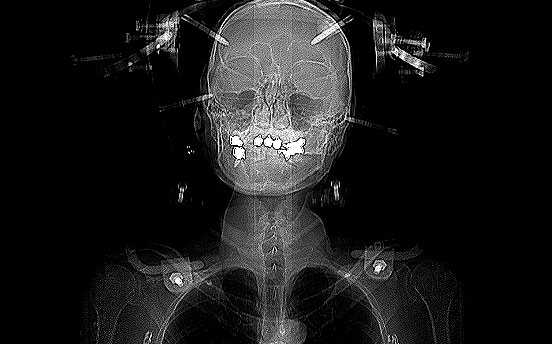

移動した後、医者から頚椎の2番目が骨折、3番目が脱臼しているため、手術が必要なことを伝えられる。

頭を固定するハローベストを付けることを同意されられる。

ハローベストを付ける。

事故当日、検査により頚椎の骨折が判明した後に取り付けられた。

4つのボルトを頭蓋骨に固定する。ボルトのついたリングを胸に装着するベストに固定し、頭が動かなくする。

4つのボルトを頭蓋骨に固定する方法は、ボルトを埋め込む場所に麻酔の注射を打ちながら、ねじ込んでいく。

CT

毎日、ピンが埋め込まれた部分を消毒し、ガーゼを撒かれる。

本来は装着した状態で歩き、外出までできるとのことだが、私の場合は装着した後、体を起こした時に頭に強い痛みが出る。

左耳後ろのボルトの打ちどころが悪かったらしい。

手術日が延期された後、ボルトを打つ場所を変更してもらった。

その効果か、体を起こしても痛みが出なくなり、体を起こし歩行のリハビリができるようになった。

手術の時の意識のない時に取り外される。